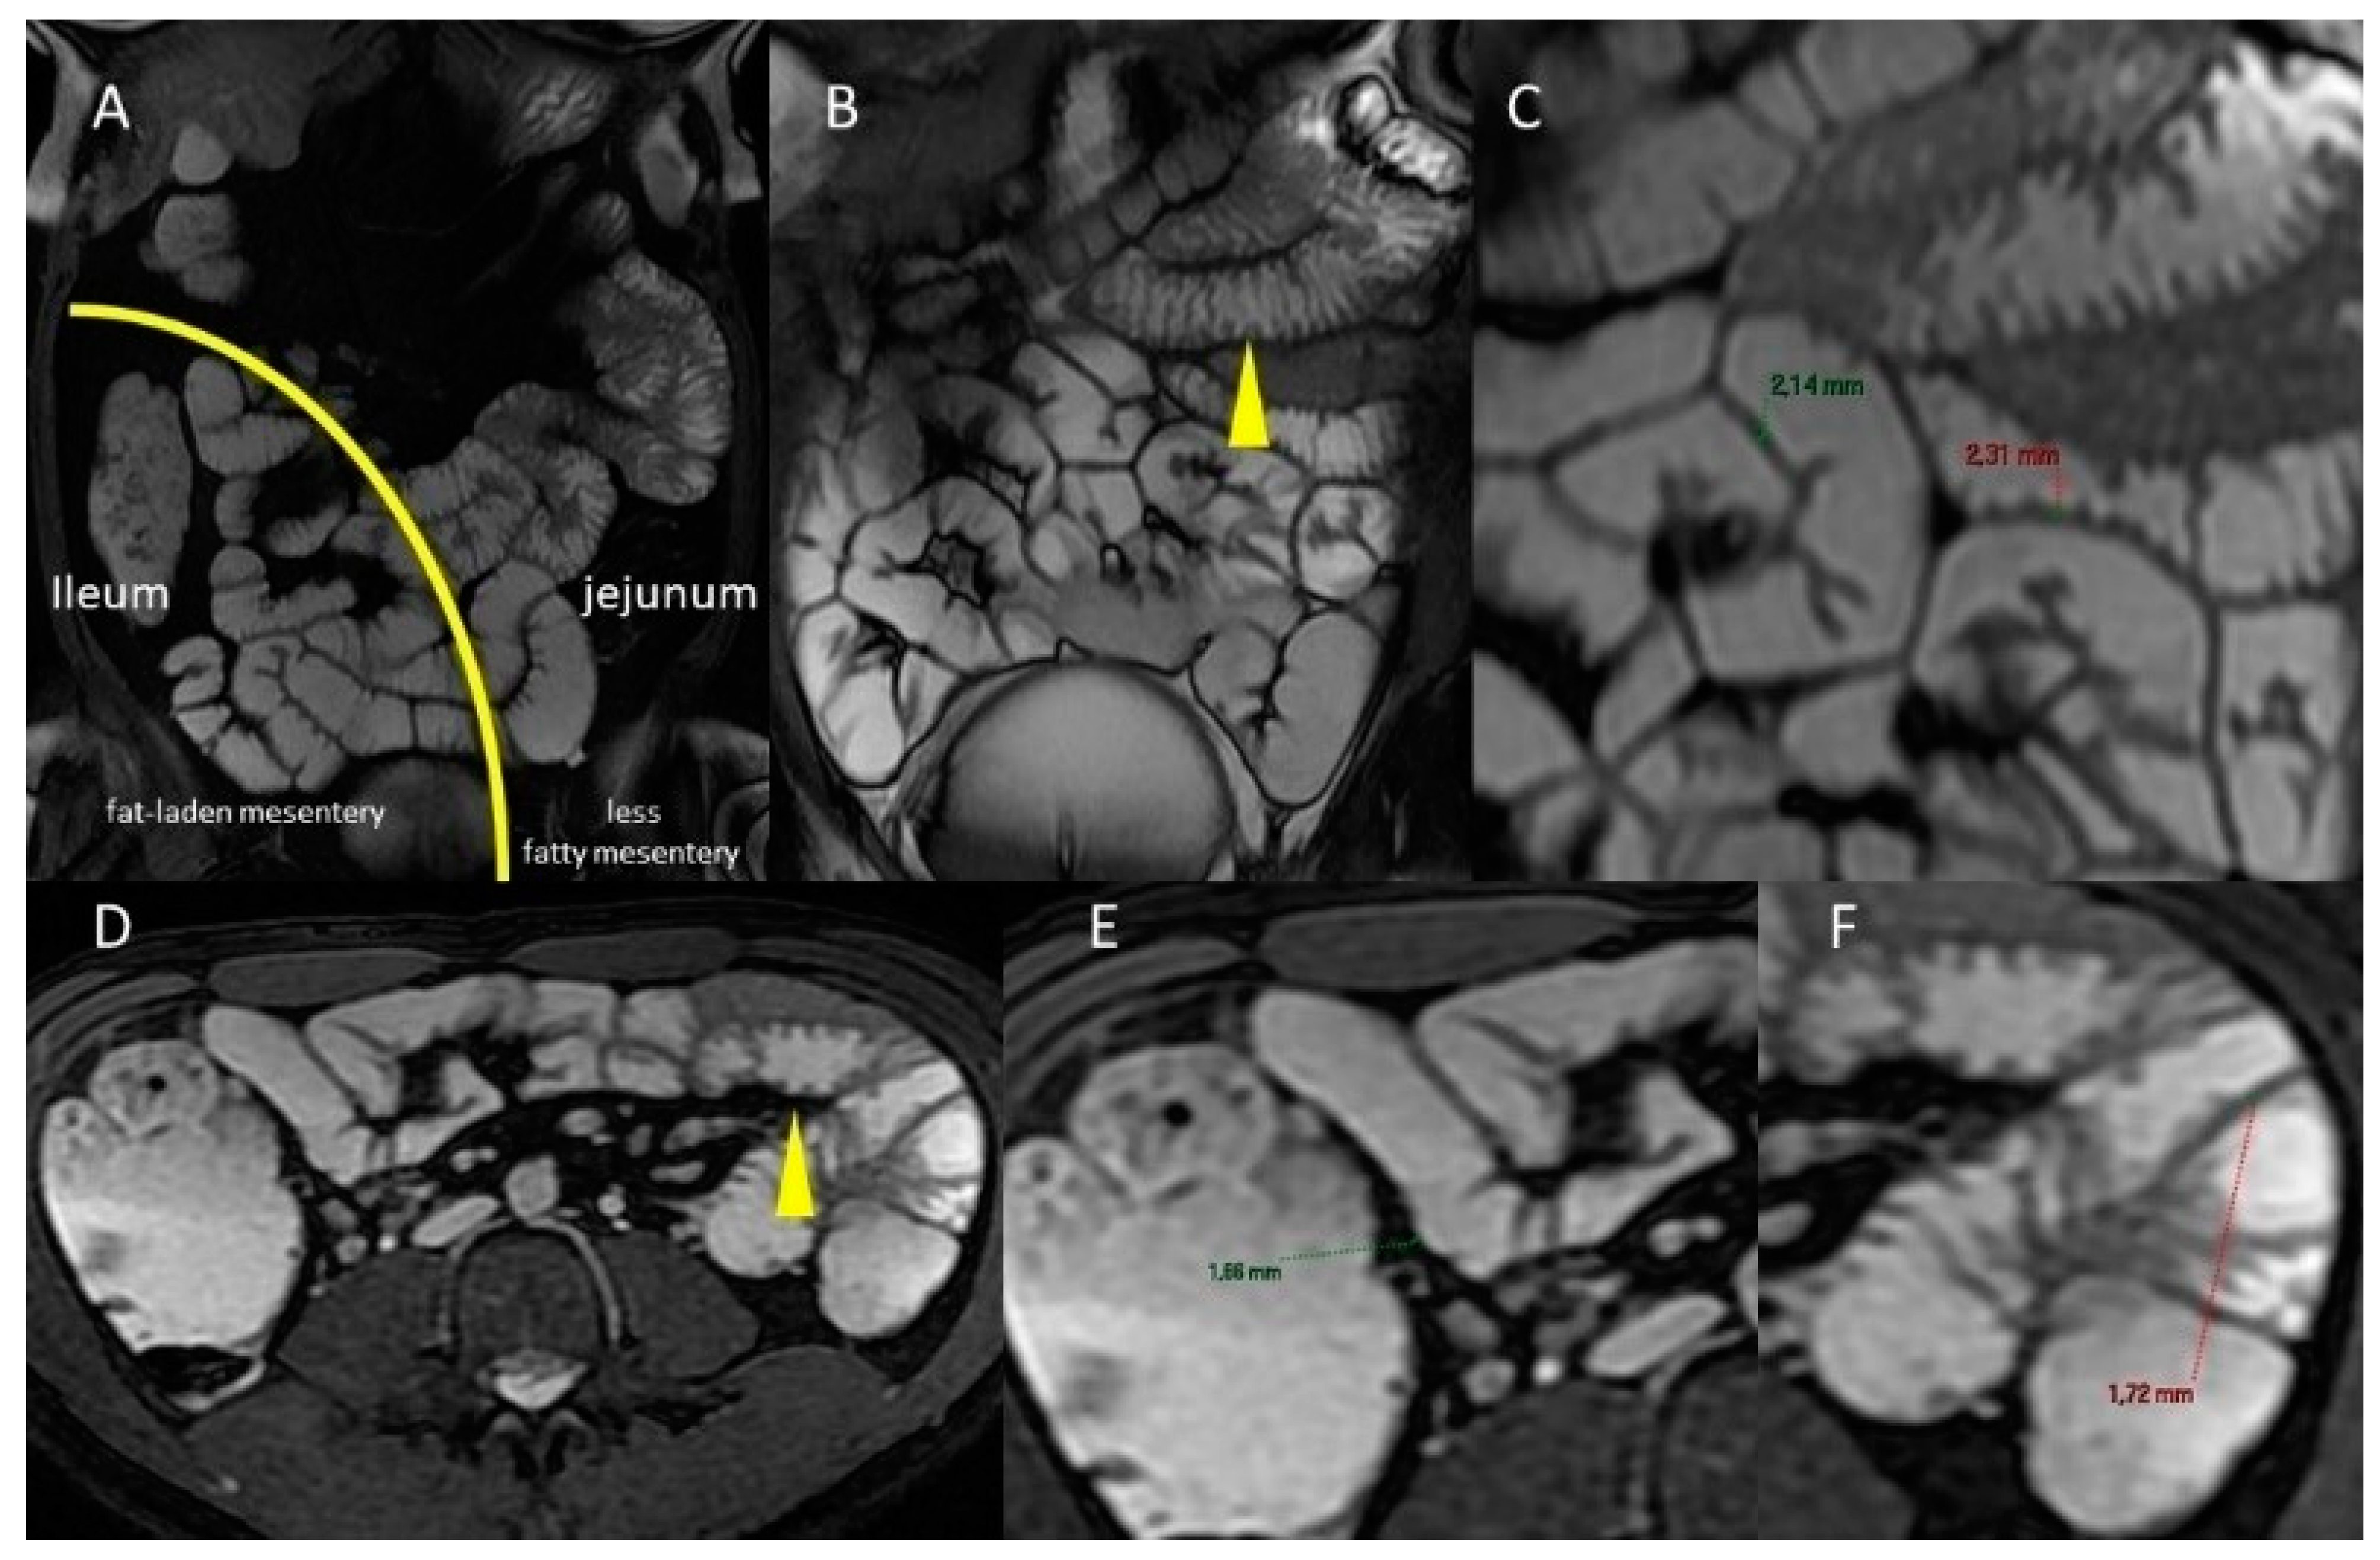

- Cronin, C.G.; Delappe, E.; Lohan, D.G.; Roche, C.; Murphy, J.M. Normal small bowel wall characteristics on MR enterography. Eur. J. Radiol. 2010, 75, 207–211. [Google Scholar] [CrossRef]

| Jejunum | Proximal Ileum | Distal Ileum | Terminal Ileum |

|---|---|---|---|

| 24.5 mm (S.D. = 4.2 mm) | 19.5 mm (S.D. = 3.6 mm) | 18.9 mm (S.D. = 4.2 mm) | 18.7 mm (S.D. = 3.6 mm) |